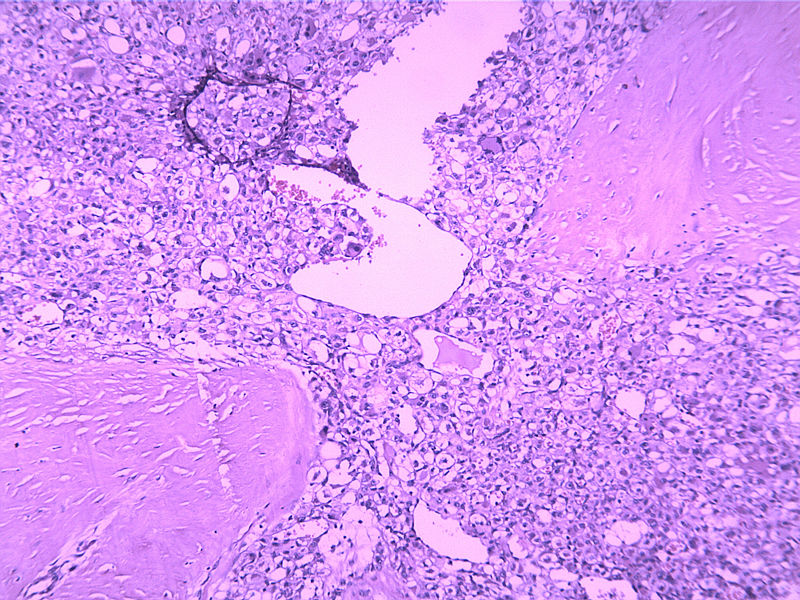

女30Y,大腿肿物5Y,直径3cm

• 女30Y,大腿肿物5Y,直径3cm图4

图4

Micro description

● Well circumscribed but non-encapsulated with infiltrative borders

● At least focal typical liposarcomatous areas

● Pleomorphic cells cover > 65% of cut surface with MFH-like, round cell liposarcoma-like (without vascular network), spindle cell liposarcoma-like or epithelioid cells (Mod Path 1999;12:722)

生长位子比较深,浸润纤维间质之中,诊断圆形细胞脂肪肉瘤 ,查一下免疫组化,S-100,VimE。及PCK排除一下上皮来源的印戒细胞癌。

本例可能是具有非典型性组织学特征的腺泡状软组织肉瘤

腺泡状软组织肉瘤的边缘常看见扩张的静脉,并常见脉管浸润,很类似于副节瘤或血管周细胞瘤